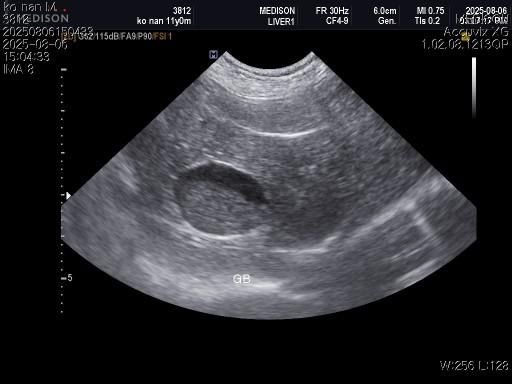

1) 혈액검사와 엑스레이 그리고 초음파상 혈뇨의 원인이 나타나지가 않는지 궁금합니다.

2) 그리고 전립선 비대가 있는지도 없는지 여부가 궁금합니다.